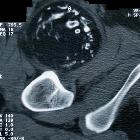

CT

The mass appears as a rounded lesion with central fat attenuation and peripheral calcification .